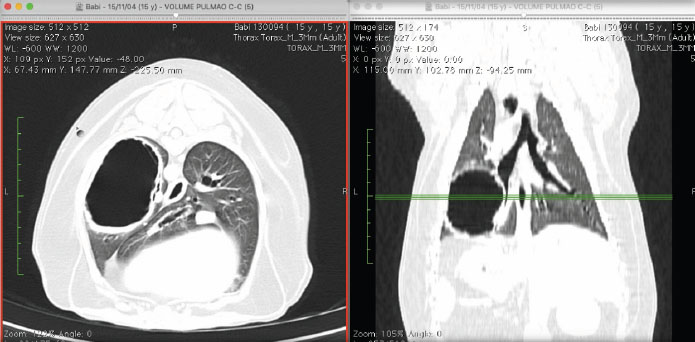

A 15-year-old mixed breed bitch, castrated, with approximately 14 kg, had sporadic coughing. Approximately 1 month before the appointment, the coughing became more frequent, she was tired easily and intolerant to physical exercise. The bitch was examined in a diagnosis center and a thoracic radiography was performed, in which we observed a large cystic emphysematous area, with thick and irregular walls, located in the left caudal pulmonary lobe (Fig. 1). The lesion measured 8.0 × 7.5 × 3.0 cm and pressed the bronchial branching of the caudal left lobe. We also observed thickening of bronchial walls, compatible with bronchopathy (Fig. 1).

Fig. 1. Thoracic radiographic images in ventrodorsal (left) and lateral (right) views, in which we observe a big cystic emphysematous area. This area has thick and irregular walls and is located in the left caudal lung lobe. It is pressing the bronchial branching of the left caudal lung lobe. We also observe thickening of the bronchial walls.